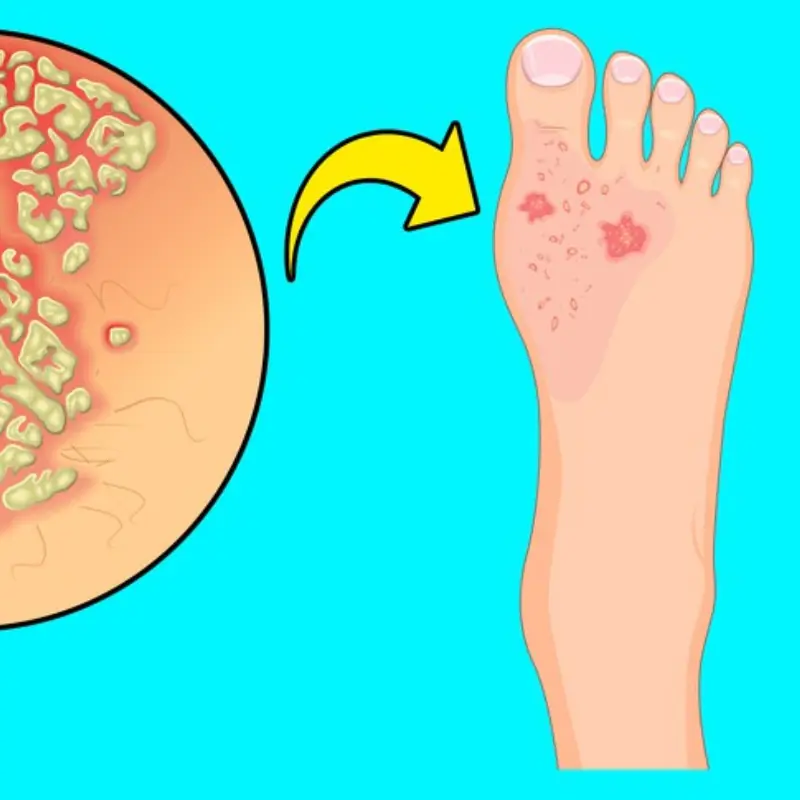

6 Simple Ways to Reduce Water Retention — and What Your Swollen Feet May Be Telling You

Swollen feet, puffy ankles, or tight shoes at the end of the day can be frustrating—and sometimes alarming. While occasional swelling is common after long hours of standing, travel, salty meals, or hormonal shifts, frequent or sudden water retention may be your body’s way of asking for attention.

Water retention (also called edema) happens when excess fluid builds up in tissues. It may show up in the legs, feet, hands, face, or abdomen, and can be caused by lifestyle habits, medications, or underlying medical conditions.

When Water Retention Could Be a Warning Sign

Occasional swelling is usually harmless—but persistent or worsening edema may suggest an underlying issue such as:

-

Kidney problems

-

Heart disease or heart failure

-

Liver disease

-

Thyroid imbalance

-

Venous insufficiency or blood clots

If swelling appears suddenly, becomes painful, or is paired with fatigue, dizziness, or breathing trouble, don’t self-treat—get medical advice early.

Bottom Line

Water retention is common—but it’s not something you should ignore. For many people, the solution begins with small, daily habits: less salt, more water, movement, leg elevation, potassium-rich foods, and reduced sugar.